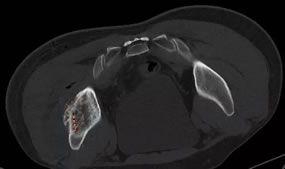

6月24日,我院介入科林征宇主任、陈锦主治医师及其团队成功开展福建省首例3D打印导向模板引导下的放射性粒子植入手术。此患者为男性,40岁,肝癌术后1年余,发现左髂骨转癌半年,行外放疗+索拉非尼靶向治疗后肿瘤残留,症状表现为左髋部疼痛,站立及行走时明显,影响日常生活及睡眠。根据患者术前的CT图像,医疗团队在PROWESS TPS软件中确定肿瘤的大小、位置及与危及器官的毗邻关系,利用计算机模拟设计一个与体表完全吻合的模板,并在模板上设计出植入粒子的“针道”,按照瘤体照射剂量的TPS计划设计每个“针道”的深度、角度及植入粒子的数目,精心的术前准备使得术后结果与术前计划高度吻合,做到了更加便捷、精准、微创,使瘤体局部放射学剂量最优化。

术前设计进针路线和粒子规划 术后对比DVH放射剂量分布均匀